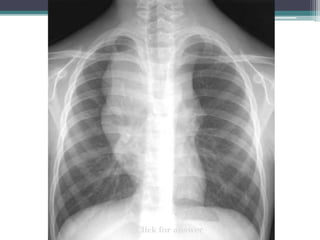

Click for answer

Can you

see the

outline of the

mass below

the diaphragm?

Thoracoabdominal sign

โ€ข Answer: Margin of mass is apparent and below

diaphragm, therefore this must be in the middle or

posterior compartments where it is surrounded by

lung

โ€ข This example is a โ€˜Lipomaโ€™